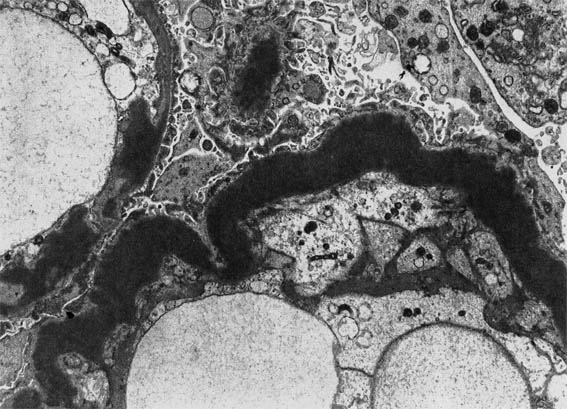

Figura 8.

Microscopía electrónica, aumento original X6.000.

Figura 9.